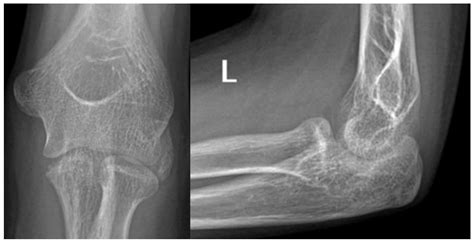

In some cases, the coronoid process in mandible may be fractured due to trauma or injury. A fracture of the coronoid process can result in difficulty opening the mouth, pain, and swelling. Treatment for a fractured coronoid process may involve immobilization, medication, or surgical repair, depending on the severity of the injury.

• Fractures: Traumatic injuries to the mandible can result in fractures of the coronoid process in mandible. These fractures can be isolated or part of a more extensive mandibular fracture pattern.

In cases of traumatic death, the coronoid process in mandible can provide clues about the nature and mechanism of injury. For example, fractures of the coronoid process in mandible can indicate blunt force trauma to the jaw, while avulsion injuries can suggest a high-velocity impact. Forensic anthropologists use this information, along with other skeletal evidence, to reconstruct the events leading to death and determine the cause of death.